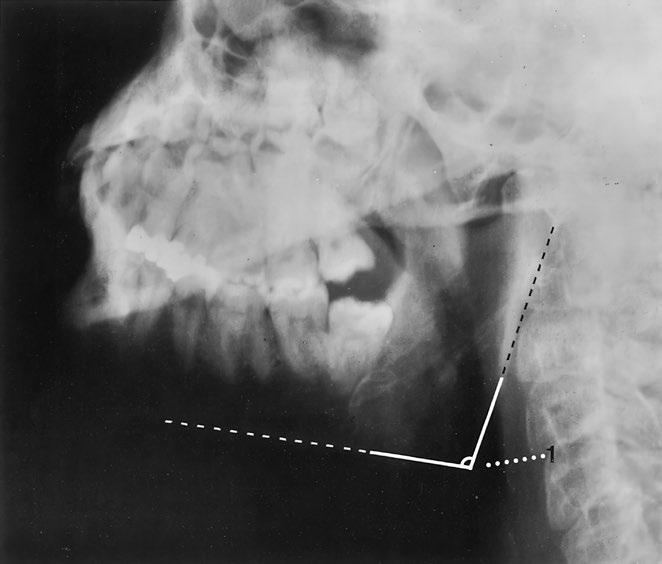

Rameno dolní čelisti

Zobrazený úsek dolní čelisti je svým tvarem a velikostí normální Čelistní úhel náležitý Mineralizace a kostní struktura jsou normální Hladké a ostré kontury normálně široké kortikalis bez patologických přerušení kontinuity

Normální tvar a postavení kostěných částí podílejících se na čelistním kloubu, hladké kontury Stav chrupu nenápadný, sanovaný Bez známek kalcifikací měkkých tkání nebo rentgenkontrastních cizích těles

Závěr

Normální zobrazení ramena dolní čelisti a čelistního kloubu

Kontrolní seznam

Tvar – šířka (hypertrofie, atrofie)

– čelistní úhel (viz níže)

– konfigurace processus condylaris a muscularis mandibulae

Struktura – mineralizace

– spongióza pravidelně uspořádaná a ostře ohraničená

– bez zhutnění, projasnění (podél kořenů zubů, např bublinkovitá)

– parodontální štěrbiny nejsou rozšířené

Kontury – intaktní

– hladké a ostré ohraničení

– bez ohraničených rozšíření nebo ztenčení

– canalis mandibulae: průběh, kontura (schody?)

Kloub

– kontura kloubní hlavice hladká

– artikulace v jamce

– tuberculum articulare: tvar, kontura (hladká)

Důležité údaje (1) Čelistní úhel asi 110–140°

Stav chrupu (zbývající skus): 2 moláry, 2 premoláry, 1 špičák, 2 řezáky, 1 zub moudrosti (v polovině dolní čelisti)